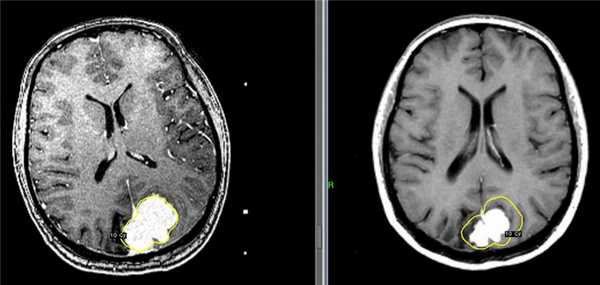

Слева – МРТ пациентки К., 47 лет. Обратилась в Клинику радиохирургии МИБС с диагнозом: рецидив после хирургического удаления парасагиттальной менингиомы верхней трети ВСС и фалькса. Размер опухоли 31 мм х 46 мм х 34 мм, объем 19 см3. Проведен сеанс стереотаксической радиохирургии. Доза по краю опухоли 10 Гр (показана желтым цветом).

Справа – контрольное МРТ пациентки К. через 6 месяцев после радиохирургического лечения на Гамма-ноже в Клинике радиохирургии МИБС. Отмечается выраженное уменьшение опухоли. Размер опухоли 19 мм х 31 мм х 24 мм, объем 7,2 см3. Уменьшение объема на 11,8 см3 (на 62%). Для наглядности желтым цветом приведена доза по краю опухоли на день лечения.